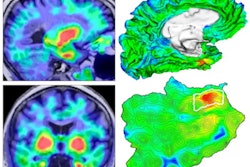

Albrecht's team found that areas of the brain with higher tau levels had diminished blood flow -- particularly in the inferior temporal gyrus, which is often the first to show tau buildup in Alzheimer's disease.

Brain regions with a negative correlation between blood flow and tau. Alzheimer's disease and mild cognitive impairment (AD-MCI) on the left, cognitively normal (CN) on the right. Image courtesy of Albrecht et al and the Journal of Neuroscience."The correlation between tau and vascular function was stronger in people with greater cognitive impairment and higher [beta-amyloid] levels," the society said in its statement. "It also appeared in more brain regions as the disease progressed in severity."